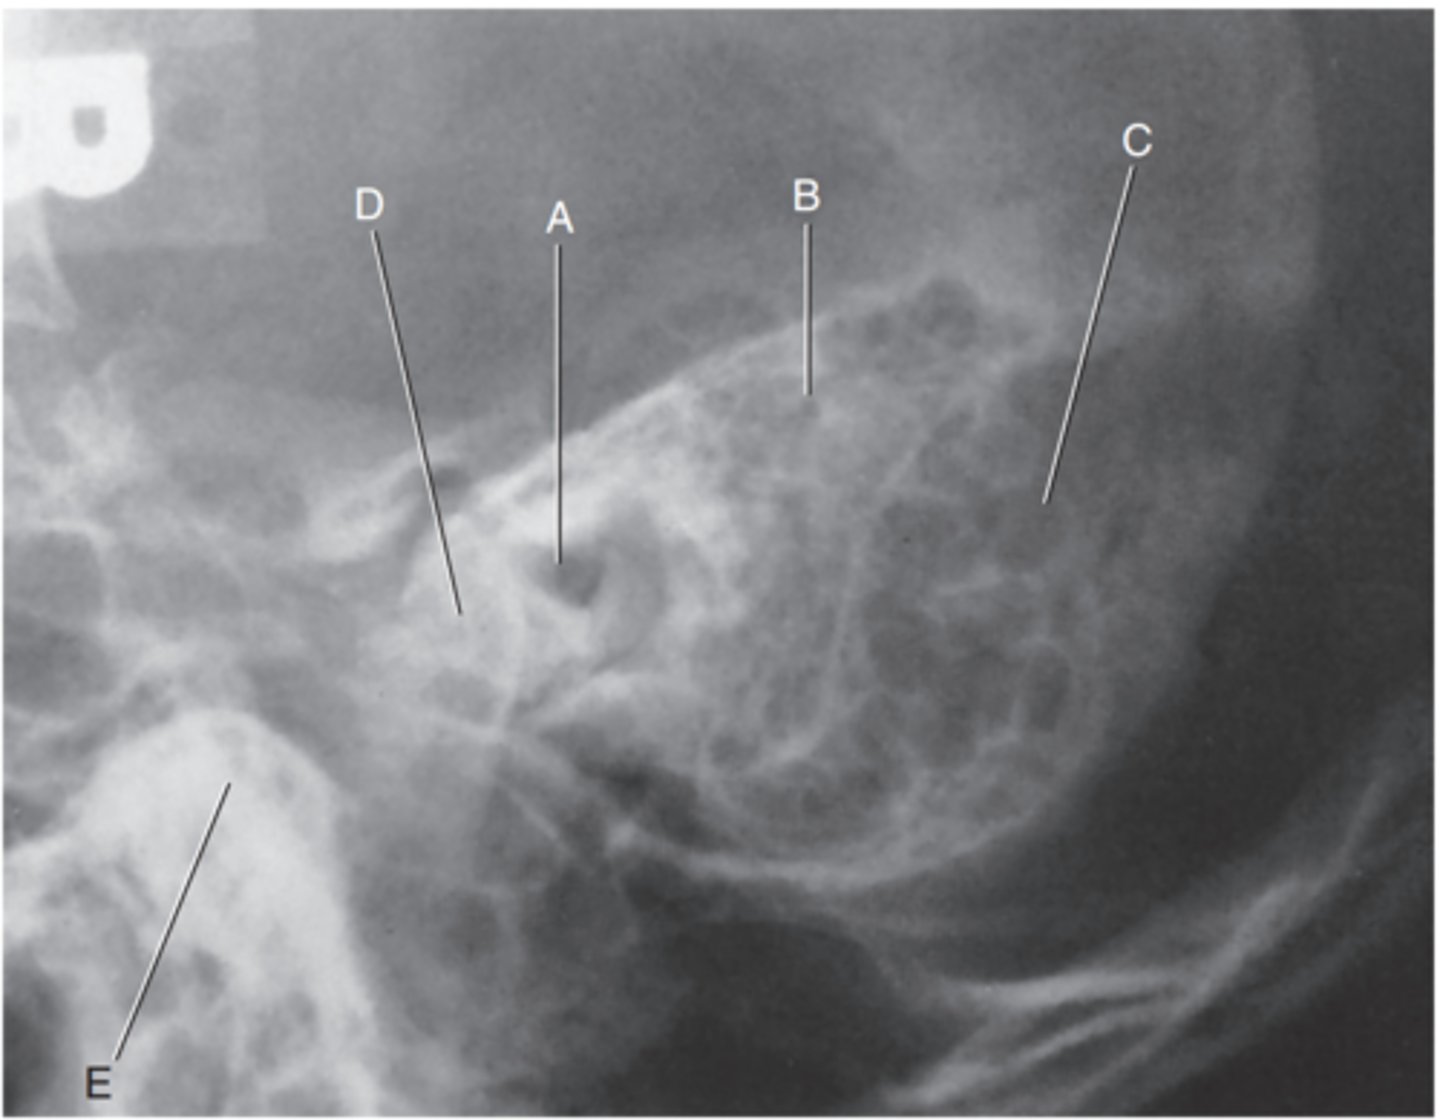

Petrous ridge

Label A

Bony (osseous) labyrinth (semicircular canals)

Label B

EAM

Label C

Region of internal acoustic canal

Label D